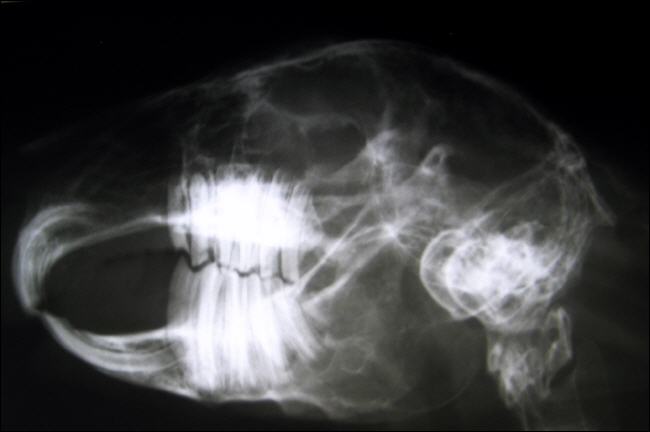

Röntgenbild der Zähne eines Kaninchens

Kaninchen: Röntgen - Zähne

Diagnose und Behandlung: Um eine Zahnerkrankung diagnostizieren zu können , muss die Maulhöhle sorgfältig untersucht werden. Ein exakter Überblick kann jedoch nur unter Sedierung / Narkose des Tieres erfolgen. Sollten sich Zahnspitzen oder Fehlstellungen finden, müssen Röntgenbilder angefertigt werden. Überwachsene Scheidezähne werden mit einer Trennscheibe / Fräser gekürzt. Das Abknipsen mit einer Zange führt meist zum Splittern der Zähne und sollte vermieden werden. Spitzen und Kanten an den Backenzähnen sowie überwachsene Backenzähne werden mit einer speziellen Fräse abgeschliffen.